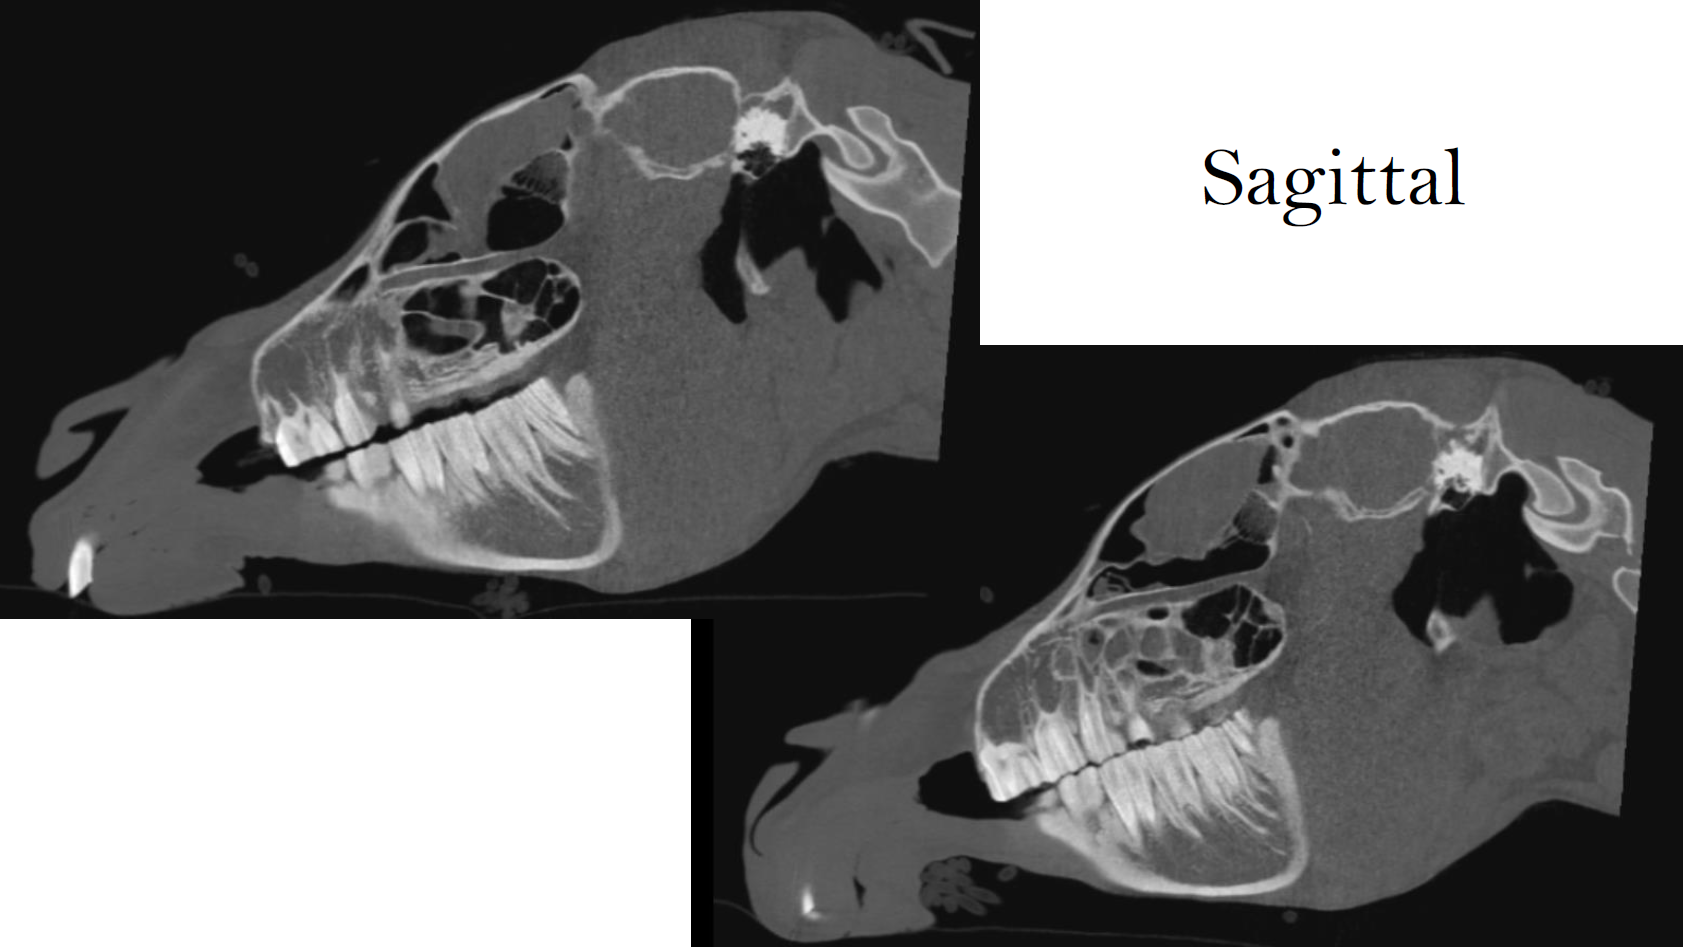

Case Example: 15‑Year‑Old Welsh Mare, Courtesy of Cotts Equine Hospital

Multiple traumatic kicks to the head with concern over damage to left mandible and TMJ. The patient was dull with abnormal left optical reflexes and a droopy left ear/muzzle consistent with nerve damage, she was hypersalivating with difficulty swallowing and had an increased respiratory effort and inspiratory stridor. Therefore, a head CT was performed.

CT Findings:

• Severely comminuted acute (mildly) displaced closed and non-articular fracture of the ramus/neck of the left mandible. There was no radiographic evidence of luxation nor joint incongruency of the left temporomandibular joint.

• Small acute simple complete (mildly) displaced closed and non-articular fracture of the left paracondylar process.

• Faint hypoattenuating line though the left side of the cranium (parietal bone/zygomatic arch), DDx: vascular channel considered most likely, less likely fissure.

• Severe soft tissue swelling of the left side of the head (axial and abaxial), DDx: oedema, cellulitis, hemorrhage.

• Moderate to severe narrowing of the pharynx.

• Possible hematoma formation in the left guttural pouch, DDx: concurrent collapse due to abaxial soft tissue swelling.

CT enabled accurate localization and classification of fractures and soft tissue compromise, guiding treatment planning and airway monitoring.